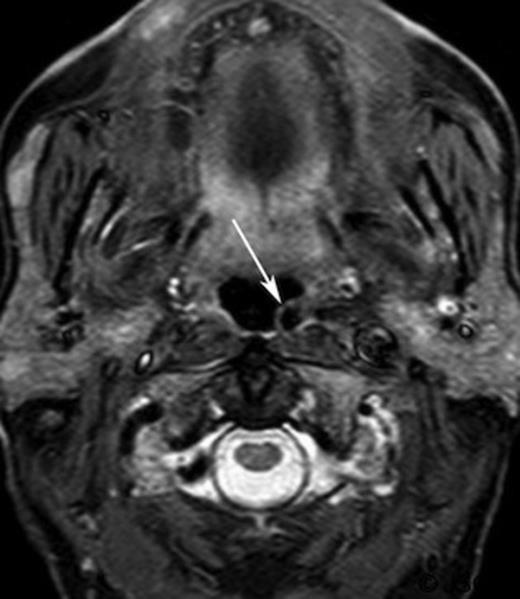

A CT scan, requested as part of his lymphoma follow-up, revealed asymmetrical fullness of the left nasopharynx due to a mass in the retropharyngeal space.(Figure 1) Owning to patient intolerance, nasoendoscopy was difficult in the clinic setting, and the nature of this swelling could not be properly determined. With the history of previous malignant disease, and the risk of recurrence or new disease being high, a biopsy was requested by the oncology team. However, since the CT imaging showed that the bulging mass could possibly be an artefact of a medially coursing left internal carotid artery (ICA), it was decided to perform a magnetic resonance imaging (MRI) prior to the biopsy. The MRI confirmed the ICA ectasia (often referred to as tonsillar loop) which manifested the asymmetry of the contour of the nasopharynx with prominence and fullness on the left just below the fossa of Rosenmuller.(Figure 2) There was no evidence of any mucosal abnormalities of nasopharynx or of the remainder of upper aerodigestive tract. No other pathological lesion was noted and the biopsy was cancelled.

Contrast enhanced axial computed tomography of parapharyngeal region showing left retropharyngeal mass (arrow)